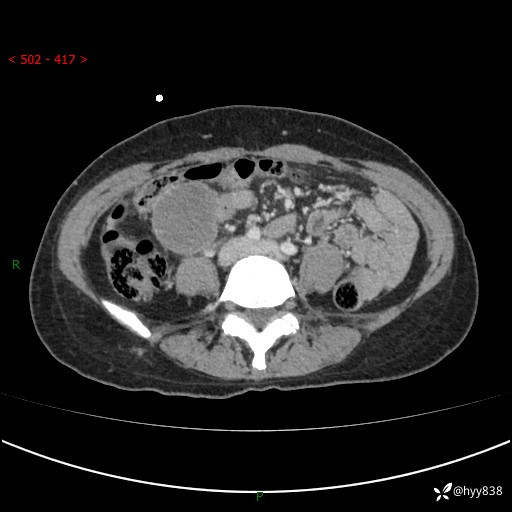

年轻女性,发现腹腔肿物1周。圆圆的肿物,诊断有难度---结果公布~

主诉:发现腹腔肿物1周

现病史:患者自诉于1周前无明显诱因出现剑突下间断性隐痛,尚可忍受,不向其它部位放射,无恶心呕吐、腹泻便秘等不适,于当地市第二人民医院就诊,行CT结果示:1.右中腹占位,间叶组织来源可能2.小肠梗阻3.盆腔积液4.腹腔积液5.副脾6.肝囊肿;于荆州二医行抗炎,抑酸,护胃,补液等对症支持治疗;患者病情好转,今为求进一步诊治,遂来我院门诊就诊,门诊以“腹腔肿瘤”收入院。 起病以来,患者精神、睡眠、饮食一般,大小便正常,近期体力体重无明显改变。

腹部CT增强(外院平扫)